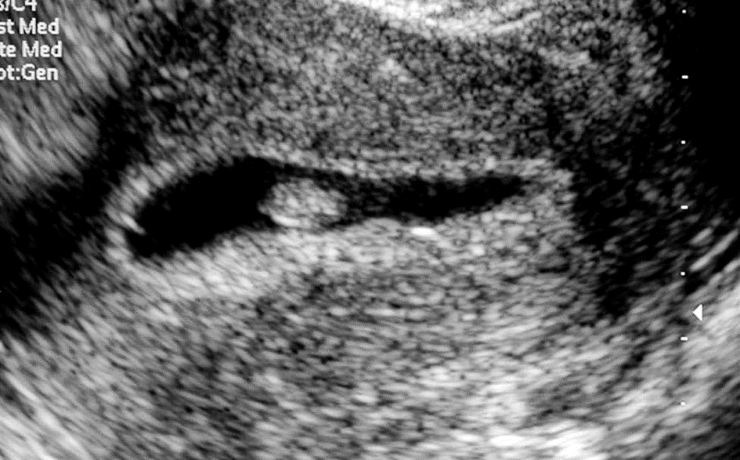

Las neoplasias de la vesícula biliar son una patología poco frecuente, pero es común que lo presenten los pacientes con alguna enfermedad autoinmune, este articulo se trata del reporte de un caso clínico de una paciente de 23 años con el diagnostico de Leiomioma. Los leiomas son tumoraciones benignas de